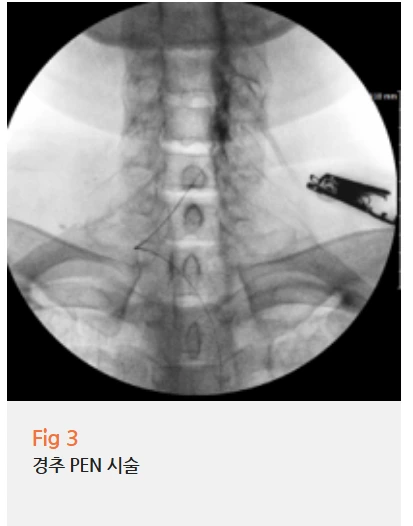

PEN(Percutaneous epidural Neuroplasty) 시술을 권해드렸습니다.

경피적 경막외 신경성형술이라고 해서,

가느다란 관을 넣어서 신경 주변의 염증과 유착을

제거하는 비수술 치료예요.